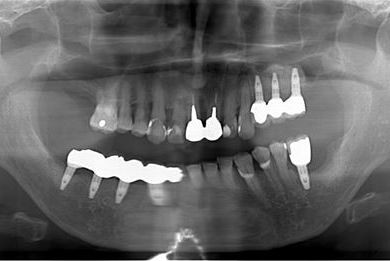

骨再生スピードインプラント治療+遊離歯肉移植

| 治療方針 | サイナスリフトにより上顎洞を拳上し、インプラント治療を可能にする。 | ||||||||||||||||||||||||||||||||

| 治療内容 | インプラント8本(サイナスリフト、抜歯即日スピードインプラント)、ハイブリッドセラミッククラウン9本、遊離歯肉移植 | ||||||||||||||||||||||||||||||||